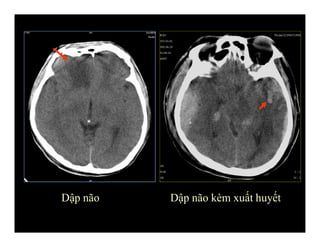

DẬP NÃO (Contusion)

Dập não Dập não kèm xuất huyết

-Do đập vàomặt trong hộp sọ, liềm-lều não -Thái dươngtrán cạnh đường giữa -Dạng tổn thương: +dập phù não: hình giảm đậm độ +nếu kèm xuất huyết não: tăng đậm độ DẬP NÃO (Contusion)

Dập não Dậpnão kèm xuất huyết